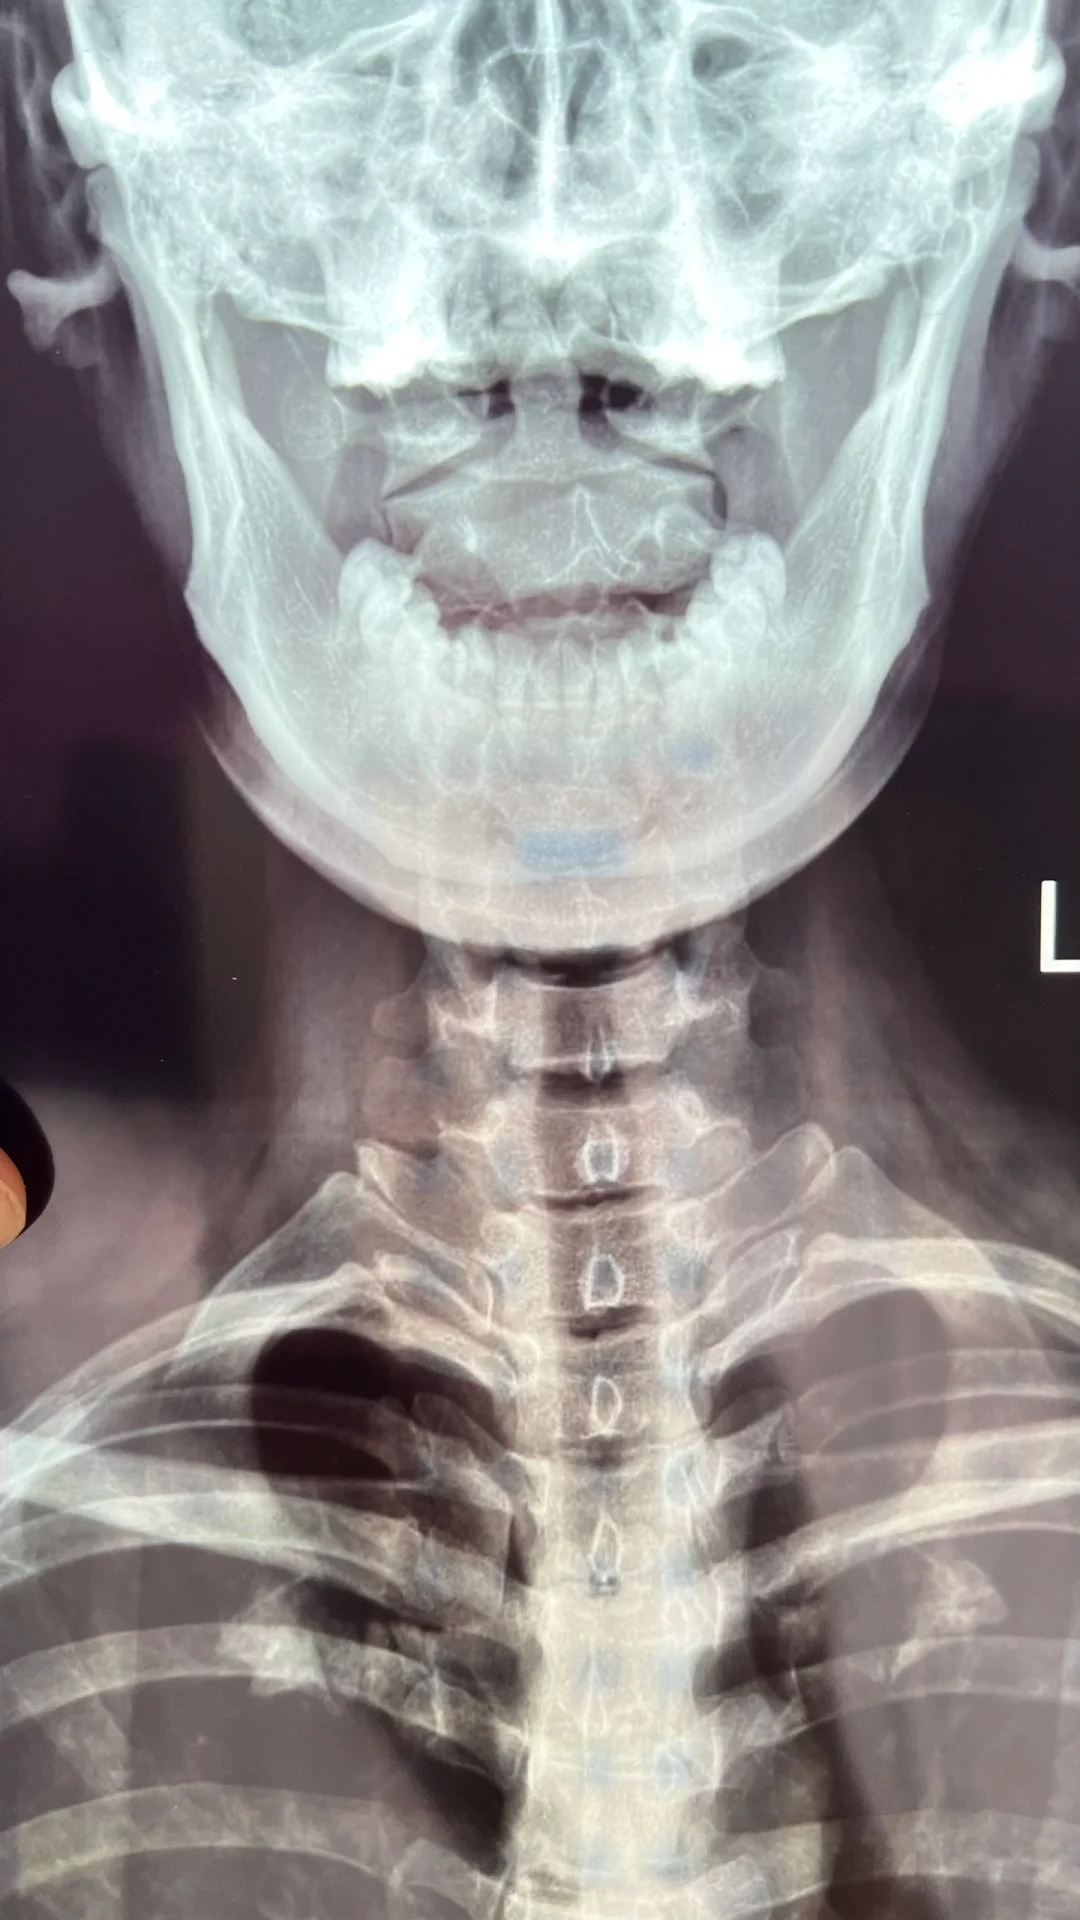

个案长期头疼 睡眠质量差甚至失眠 习惯性落枕 右侧胸锁乳突肌紧张 向右侧转头受限 眼睛干涩拍片显示 第二颈椎棘向左旋转 第一颈椎右侧横突旋前 并且第一颈椎横突向右平移 矫正了第一颈椎头向右活动幅度明显增大 头明显舒服 并且眼睛视力范围变大 矫正了第二颈椎感觉到头坐在颈椎上正了 脖子不晃了下巴自然内收了 下颌线出来了 矫正过这两个椎体人头脑清晰非常多 整个颈部肌肉都柔软了 而且两侧太阳穴特别暖说明脑供血变好